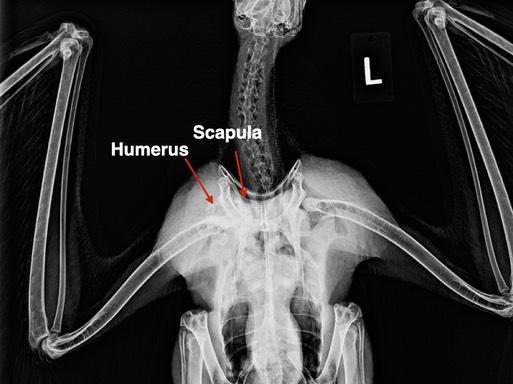

Osprey 22-234

We received special permission to admit an Osprey that had been quarantined in Washington for two weeks. Unfortunately it had fractures of the right humerus and scapula that were not repairable and was euthanized.